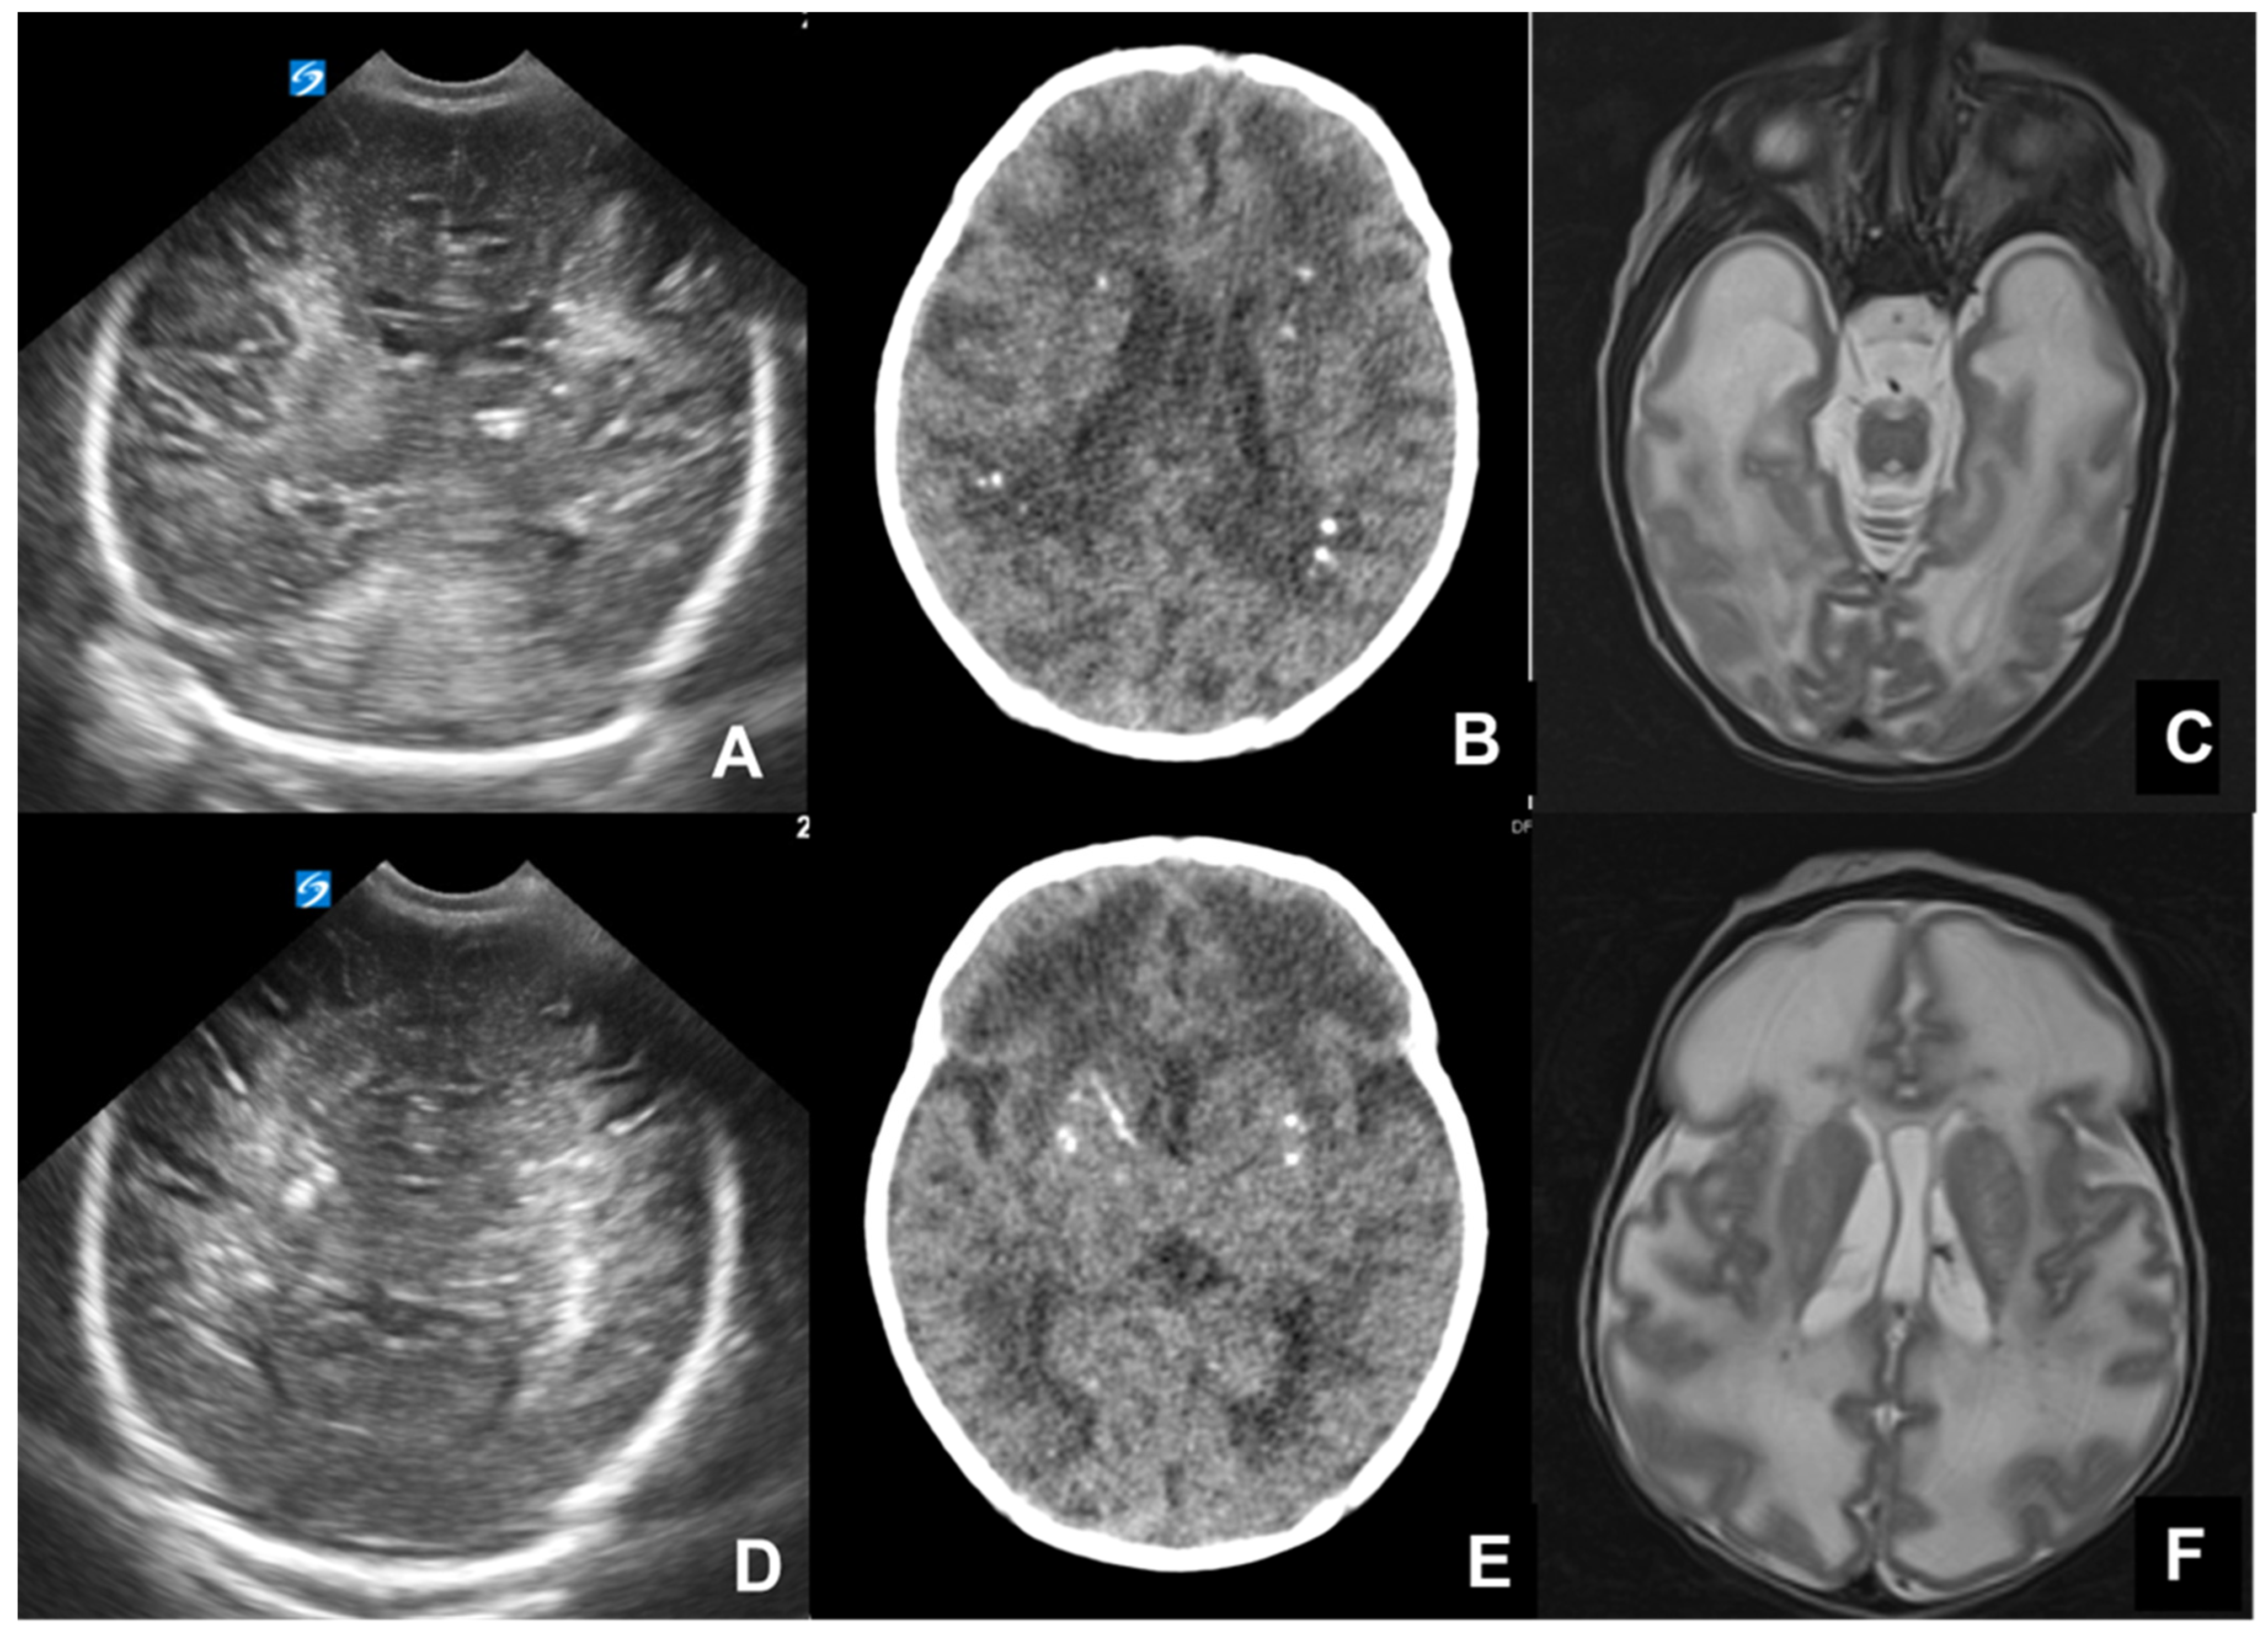

- Diebler, C.; Dusser, A.; Dulac, O. Congenital toxoplasmosis. Clinical and neuroradiological evaluation of the cerebral lesions. Neuroradiology 1985, 27, 125–130. [Google Scholar] [CrossRef]

- Jacquemard F Ultrasonographic signs of congenital toxoplasmosis. Arch. Pediatr. 2003, 10 (Suppl. S1), 35–38.

- Lago, E.; Baldisserotto, M.; Filho, J.H.; Santiago, D.; Jungblut, R. Agreement between ultrasonography and computed tomography in detecting intracranial calcifications in congenital toxoplasmosis. Clin. Radiol. 2007, 62, 1004–1011. [Google Scholar] [CrossRef] [PubMed]